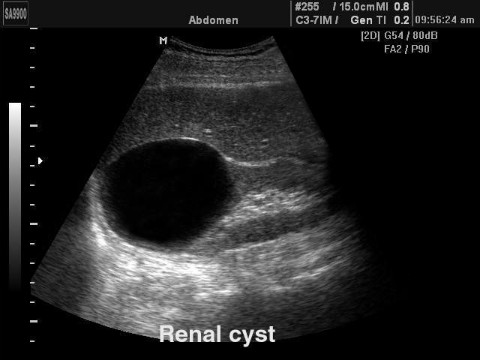

신낭종은 신장에 체액이 고여 생기는 낭종을 말하며 선천성/후천성/단순신낭종/낭성신낭종으로 나눌 수 있습니다. 신장 낭종(신장 낭종)은 신장 낭종(신장 낭종)의 수, 신장 실질이 파괴된 정도, 낭종에 다른 장기가 동반되는지 여부에 따라 분류 및 치료할 수 있습니다. 신장 낭종(신장 낭종)은 대부분의 낭종과 마찬가지로 임상적으로 거의 의미가 없는 단순한 낭종이며 그 원인은 잘 알려져 있지 않습니다. 일종의 노화 현상인 것 같아요. 드물게 신장 낭종(신장 낭종)은 크기가 매우 크거나 합병증이 있는 경우 문제가 될 수 있습니다.신장 낭종 증상

단순 신장 낭종(신장 낭종)은 일반적으로 무증상이지만 신장 낭종(신장 낭종)이 크기가 커지고 다른 장기를 누르면 통증이 발생할 수 있습니다. 드물게 신장 낭종(신장 낭종)의 감염은 발열, 통증 또는 압통을 유발할 수 있으며 신장 낭종(신장 낭종)이 확대로 인해 파열되는 경우 소변 내 혈액이 발생할 수 있습니다. 일반적으로 단순 낭종은 신장 기능 저하를 유발하지 않지만 다낭성 신장 질환은 서서히 신부전으로 진행될 수 있습니다.복부초음파

신장질환 진단에 있어 복부초음파는 가장 흔하고 비침습적이며 많은 정보를 얻을 수 있고 복막 내 다양한 장기를 관찰할 수 있다. 최근에는 건강검진 시 복부 초음파 검사를 자주 시행하여 새로운 종양을 조기에 발견하는 경우가 많습니다. 복부초음파에서 신장에 낭종이 발견되면 단순낭종인지 복합낭종인지 고형종양인지 구분할 수 있다고 합니다. 조영제를 사용한 CT 스캔이 권장됩니다.신장 낭종 치료